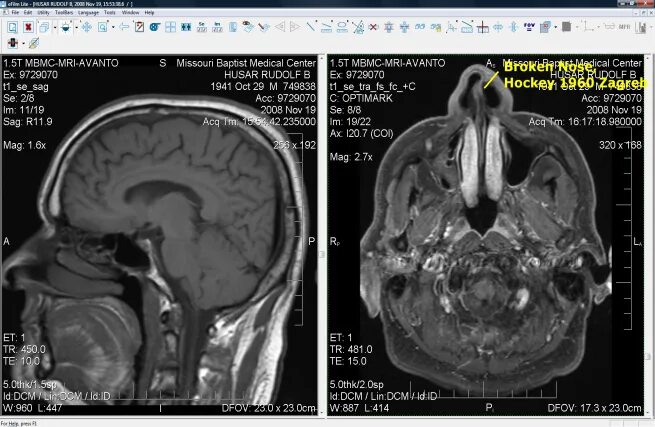

Просмотр снимков мрт